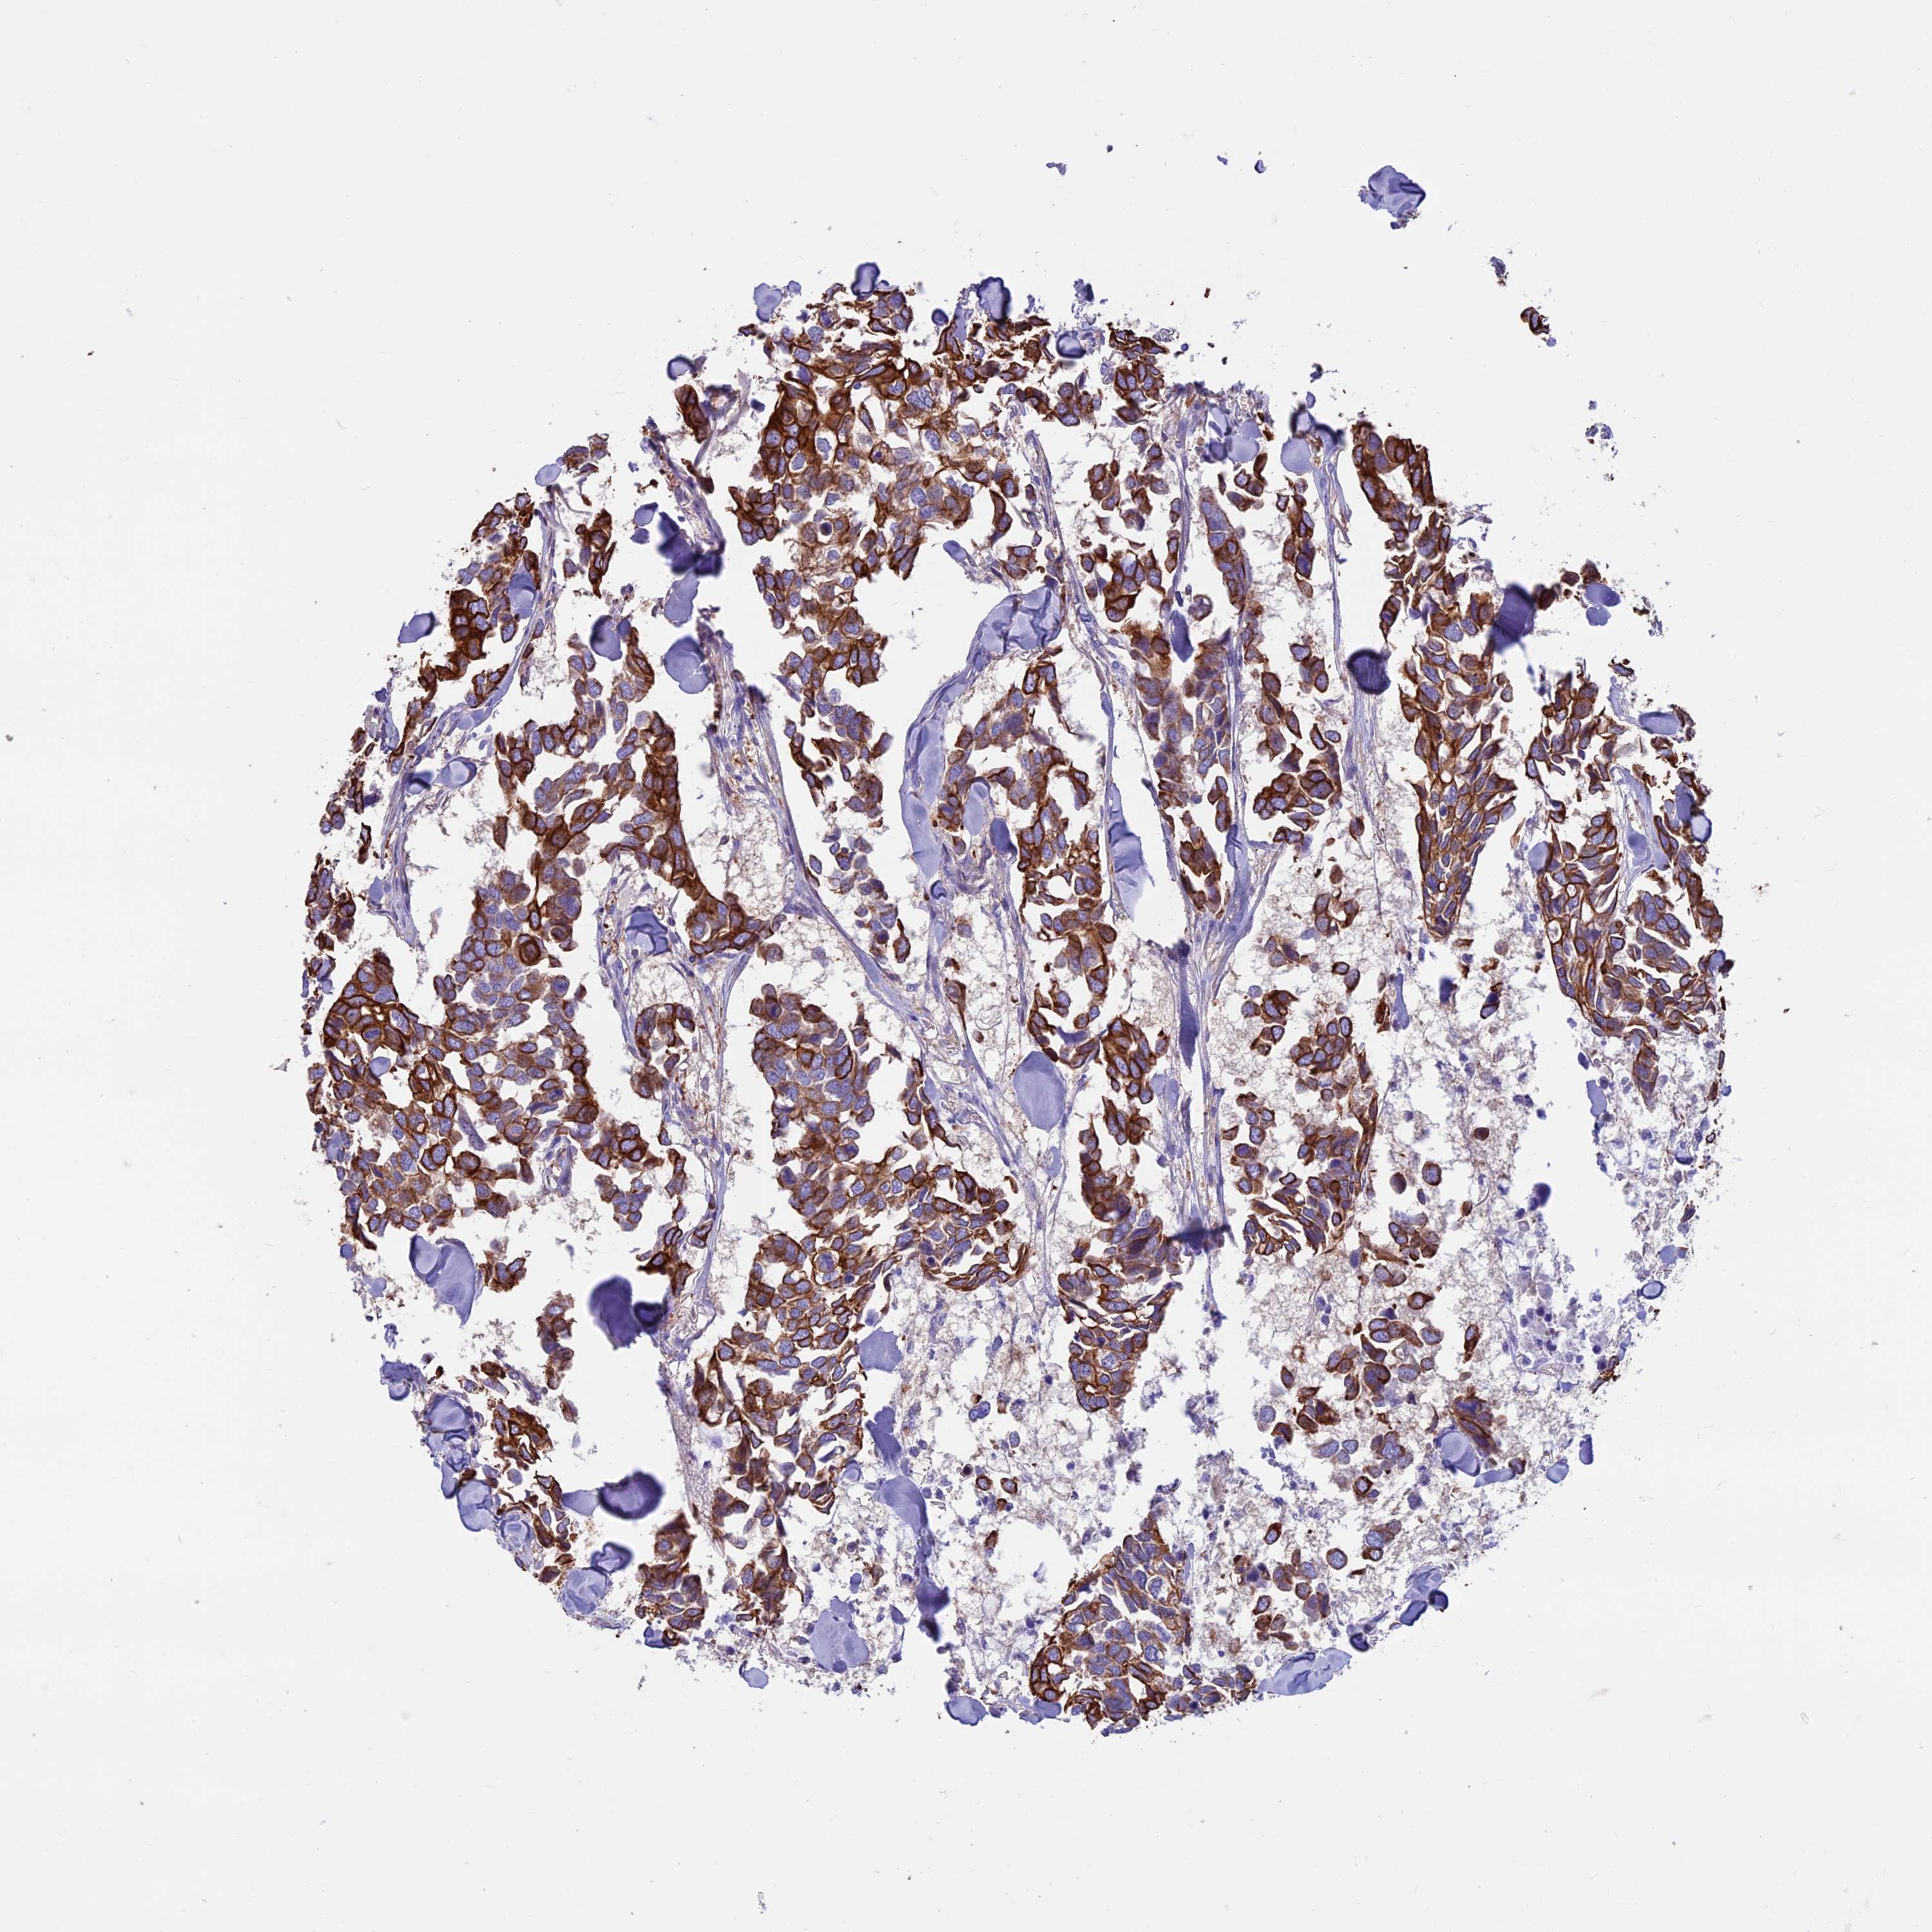

CANCER BREAST CANCER Show tissue menu

BRCA TCGA BRCA VALIDATION PROTEIN EXPRESSION